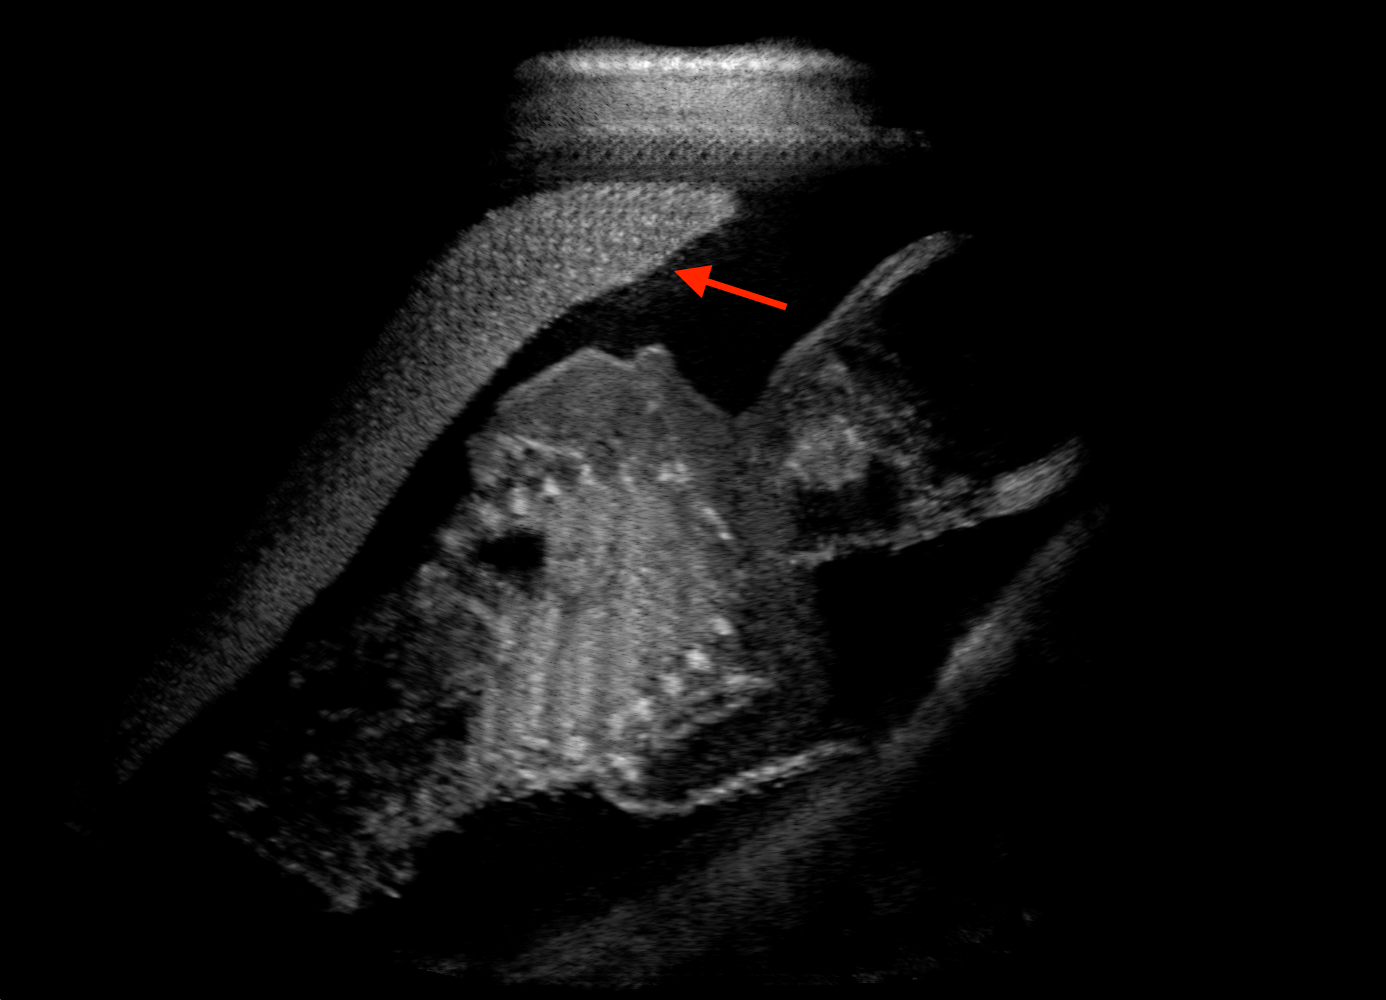

For the interpretation of the local errors, sample spatial p error maps are depicted in Fig. 3 for LSA2H, NSA2H, and SA2H for the middle two examples shown in Fig. 2. Both images generated by NSA2H have a lot of missing structures and accordingly have high error almost all over the map. Artificial skull enhancement with LSA2H is seem to evoke large p error, as shown in the corresponding error map, whereas the bright spots in the error map of SA2H reflect some hallucinated shadows and structure in the brain. All of above mentioned regions of interest are marked by red arrows. In the bottom example, SA2H fails to generate faithful content at the bottom region marked by red circles, which is well indicated by the error map as well.